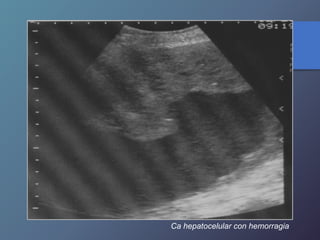

Carcinoma Hepatocelular

• Variable desde mas hipoecoicas hasta complejas o

Hiperecogénicas.

• Los chc pequeños son hipoecoicos, con halo periférico

fino que Corresponde a la capsula.

• Los chc de mayor diámetro, tienden a ser Heterogéneas,

complejas.

• Son hipervasculares, con vasos dismórficos.

Características Ecográficas

Ca hepatocelular con hemorragia